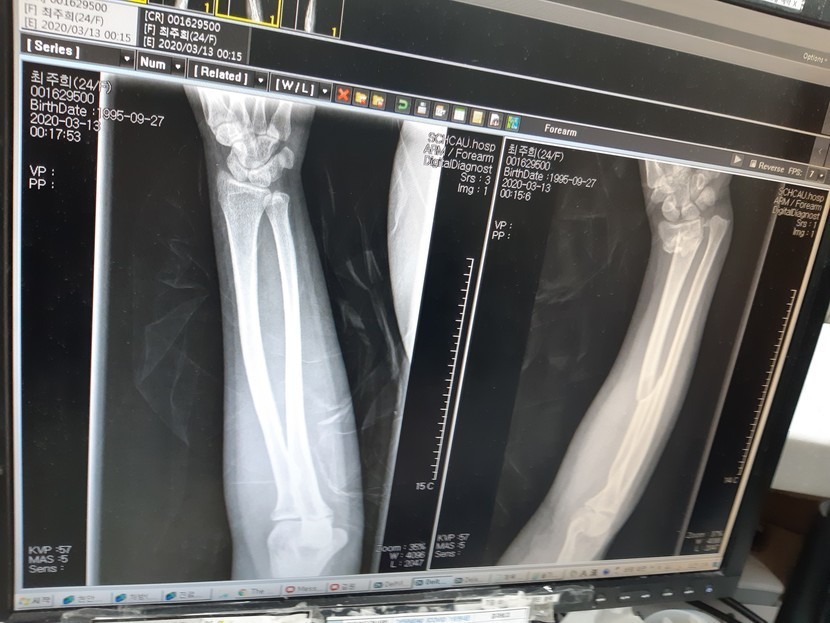

20.03.14 93 읽음 교통사고 nq6011727 구독하기 3 7 콘텐츠의 수익 13 울딸 사고가 나서 오른쪽 팔 2군데 골절되었어요 피해자는 큰소리 치며 자기 잘못 아니라고 딸아이를 혼내더래요 이렇게 병원에서 고생하고 있어요 ㅠ블랙박스 경찰에 제출했는데 신호위반을 해서 100프로 상대방 잘못으로 나왔어요 뻔뻔하죠? 정말 본인이 잘못했으면서 딸아이 혼내고 말이예요 합의 안해주고 싶네요 정말 정말 속상해요 7 0 / 300 입력